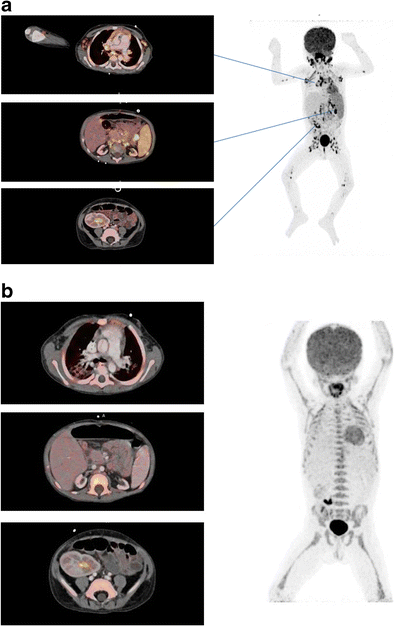

Fig. 2

figure 2

A three year old kidney and liver recipient with fever and elevated EBV DNA in plasma 3 months after transplantation, suspected for post-transplant lymphoproliferative disorders (PTLD). A) The FDG PET/CT showed increased FDG uptake in enlarged and normal sized lymph nodes above and below diaphragm including the extremities, in the rhinopharynx, tonsils, and spleen compatible with post-transplant lymphoproliferative disorders. B) Complete metabolic and structural remission after 3 weeks of rituximab treatment. The area with increased FDG-retention in the right fossa corresponds to urine excretion in the well-functioning graft